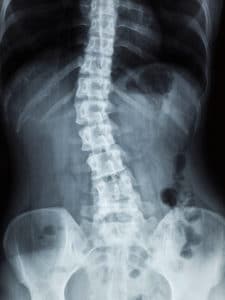

La scoliose se caractérise par une déviation permanente de la colonne vertébrale. En effet, les